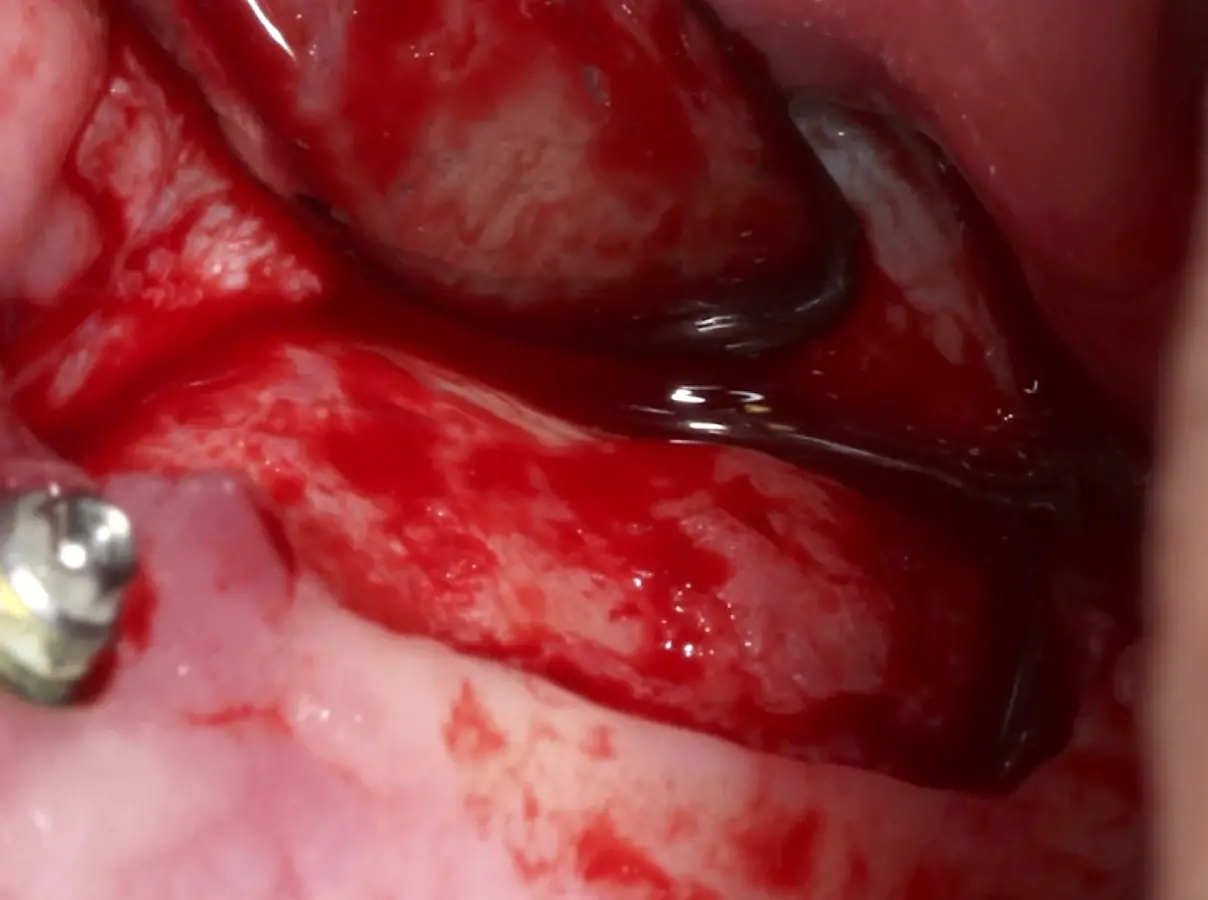

Figura 6. Técnica por retiro de la tabla ósea. Una vez retirada o fracturada la tabla ósea, se introduce el inserto de presión hidráulica entre la membrana de Schneider y los bordes de la ventana, con suaves movimientos se inicia el desprendimiento gracias al chorro de agua expulsado a través del inserto (Figura 7).

Inserto de presión hidráulica iniciando el desprendimiento de la membrana de Schneider (a, b ).

Figura 7. Inserto de presión hidráulica iniciando el desprendimiento de la membrana de Schneider (a, b ).